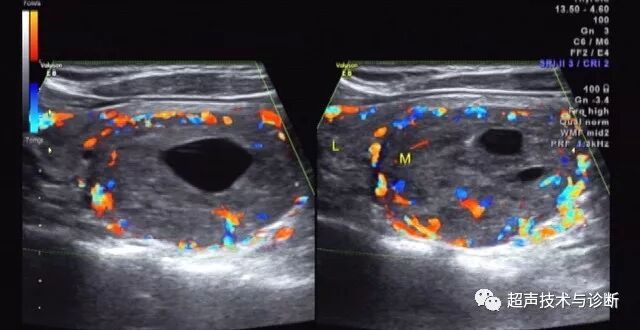

4 CDFI:结节周边声晕处可见环状包绕的血流信号,外周血流多于结节内部血流信号。

5 由于结节周边及内部血供相对丰富,微血管血流灌注较正常甲状腺组织多,因此其造影模式多为结节整体均匀高增强,周边可出现环状增强,大多数表现为“快进慢退”。

(图3-6)甲状腺滤泡型腺瘤,结节内部及周边均可见较丰富血流,周边可见环状血流信号